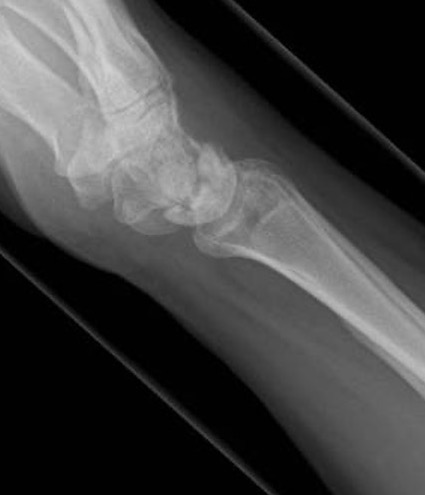

Xray

Progressive changes of AVN

- sclerosis

- fragmentation / fracture / flattenging

- midcarpal collapse: scaphoid flexion / capitate descent

- radiocarpal and midcarpal osteoarthritis

Lichtmann Classification

| Stage II | Stage IIIA |

|---|---|

| Sclerosis |

Collapse / fragmentation Normal carpal height |

| Stage IIIB | Stage IV |

|

Collapse / fragmentation Scaphoid flexed / Capitate migrates proximally |

Pancarpal osteoarthritis |